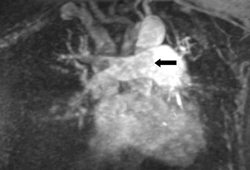

- multiple-detector computed tomographic pulmonary angiography (CTPA)

- magnetic resonance angiography (MRA)

- pulmonary angiography